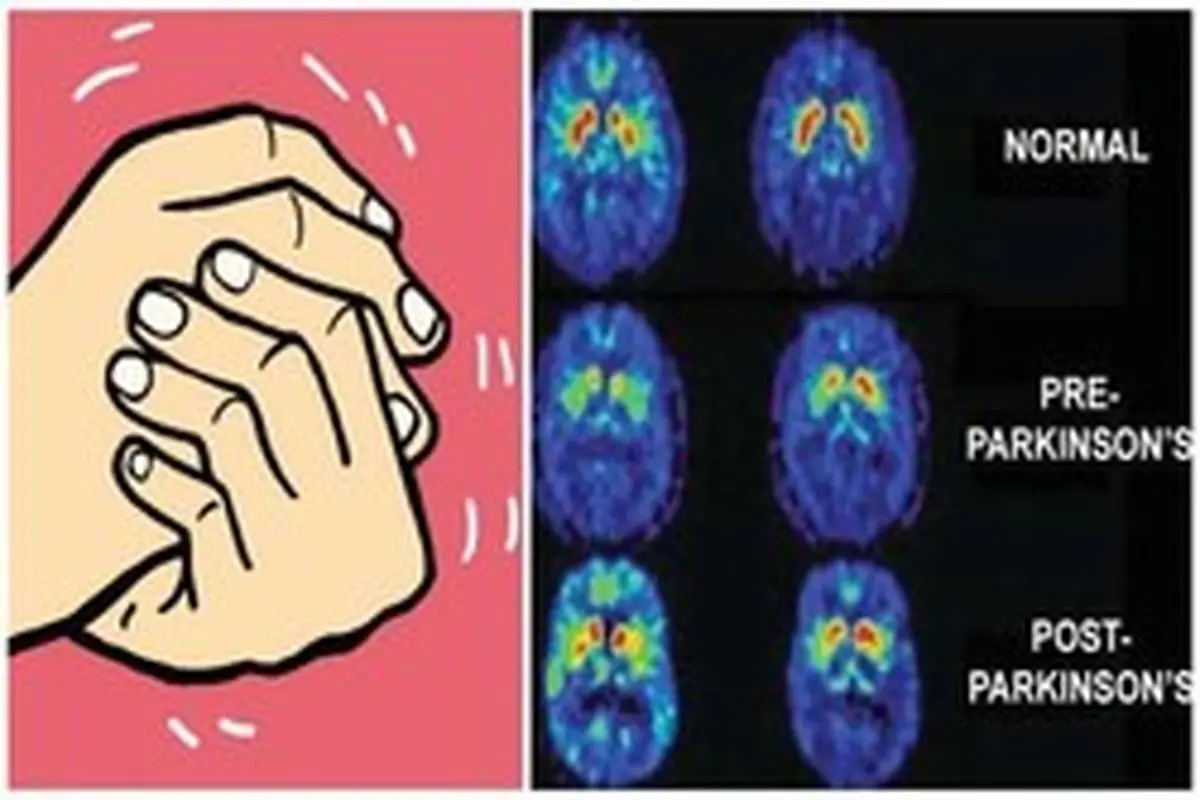

پارکینسون یک بیماری مغزی تحلیلبرنده عصبی است که درمان قطعی ندارد. شایعترین علائم این بیماری عبارتند از: لرزش دستوپا و همچنین احساس لرزش در فک و صورت، سفتی عضلات، کندی حرکت و مشکلات تعادلی.

پارکینسون یک بیماری مغزی تحلیلبرنده عصبی است که درمان قطعی ندارد. شایعترین علائم این بیماری عبارتند از: لرزش دستوپا و همچنین احساس لرزش در فک و صورت، سفتی عضلات، کندی حرکت و مشکلات تعادلی.